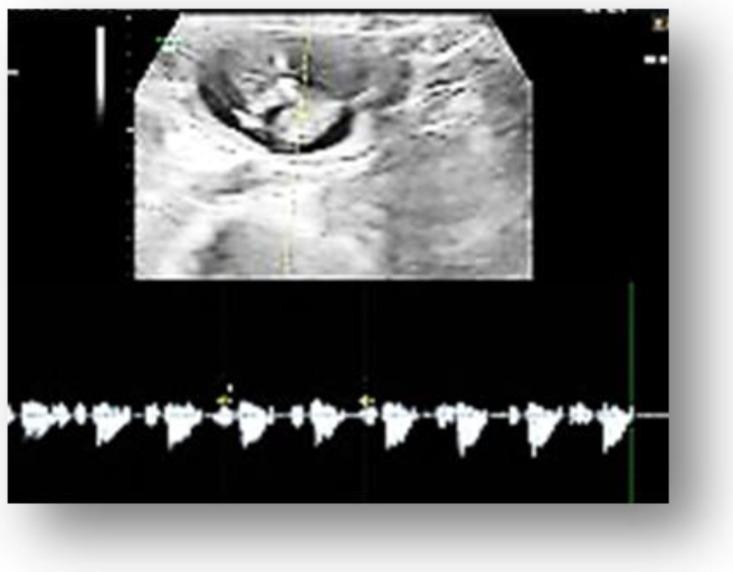

Tubal ectopic pregnancies remain a challenging and life-threatening obstetric condition in the early stages that unavoidably lead to abortion or rupture, further reflected by the associated maternal mortality. Therefore, in the present case report, we report the experience of a 36-year-old woman who presented to our Emergency Department with a history of moderate hypogastric pain, mild vaginal bleeding, and bilateral mastalgia, symptoms that started 20 days ago after uterine curettage for a declarative eight-week pregnancy. On admission, a physical examination showed regular standard signs. The ultrasound examination revealed in the left abdominal flank a gestational sac with a live fetus corresponding to the gestational age of 13 weeks. Given the position of the gestational sac, we suspected a possible abdominal pregnancy. Independently on her human chorionic gonadotropin (hCG) of 33.980 mIU/mL and hemoglobin (Hb) of 13.4 g/dL, the exact location of the pregnancy following ultrasound was hard to establish. Magnetic resonance imaging (MRI) examination was requested, after which we suspected the diagnosis of ovarian pregnancy. Given the paraclinical and clinical context of the worsening of painful symptoms, we decided to perform an exploratory laparoscopy in the multidisciplinary team (digestive and vascular surgeon) that showed the existence of a tubal pregnancy.

输卵管妊娠仍然是早期具有挑战性且危及生命的产科疾病,不可避免地导致流产或破裂,进一步反映在相关的孕产妇死亡率上。因此,在本病例报告中,我们报告了一位 36 岁妇女的就诊经历,她因中度下腹痛、轻微阴道出血和双侧乳房痛就诊于我院急诊科,这些症状在 20 天前因子宫刮宫术而出现,当时为明确的 8 周妊娠。入院时,体格检查显示正常标准体征。超声检查在左腹部外展处发现一个妊娠囊,内有一个与妊娠龄 13 周相符的活胎。鉴于妊娠囊的位置,我们怀疑可能是腹部妊娠。尽管人绒毛膜促性腺激素(hCG)为 33.980 mIU/mL,血红蛋白(Hb)为 13.4 g/dL,但仍难以确定超声检查后的妊娠确切位置。因此,我们要求进行磁共振成像(MRI)检查,之后我们怀疑为卵巢妊娠。鉴于临床症状恶化的临床和辅助检查情况,我们决定在多学科团队(消化和血管外科医生)中进行探查性腹腔镜检查,结果显示存在输卵管妊娠。